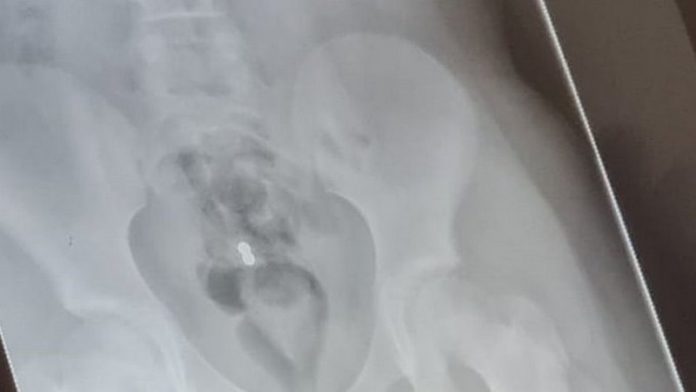

Lexi told her mum she had accidentally swallowed the magnets at around 7.50pm on Wednesday and was rushed to Whiston Hospital where staff performed an x-ray.

After consultations, Alder Hey Children’s Hospital asked Lexi to come in the following morning for further consultation where they discovered the magnets had moved from her diaphragm to her rectum.

“I took her back to Alder Hey today and they did another x-ray and found the magnets are in her bowels but they’re not ready to come out yet.”